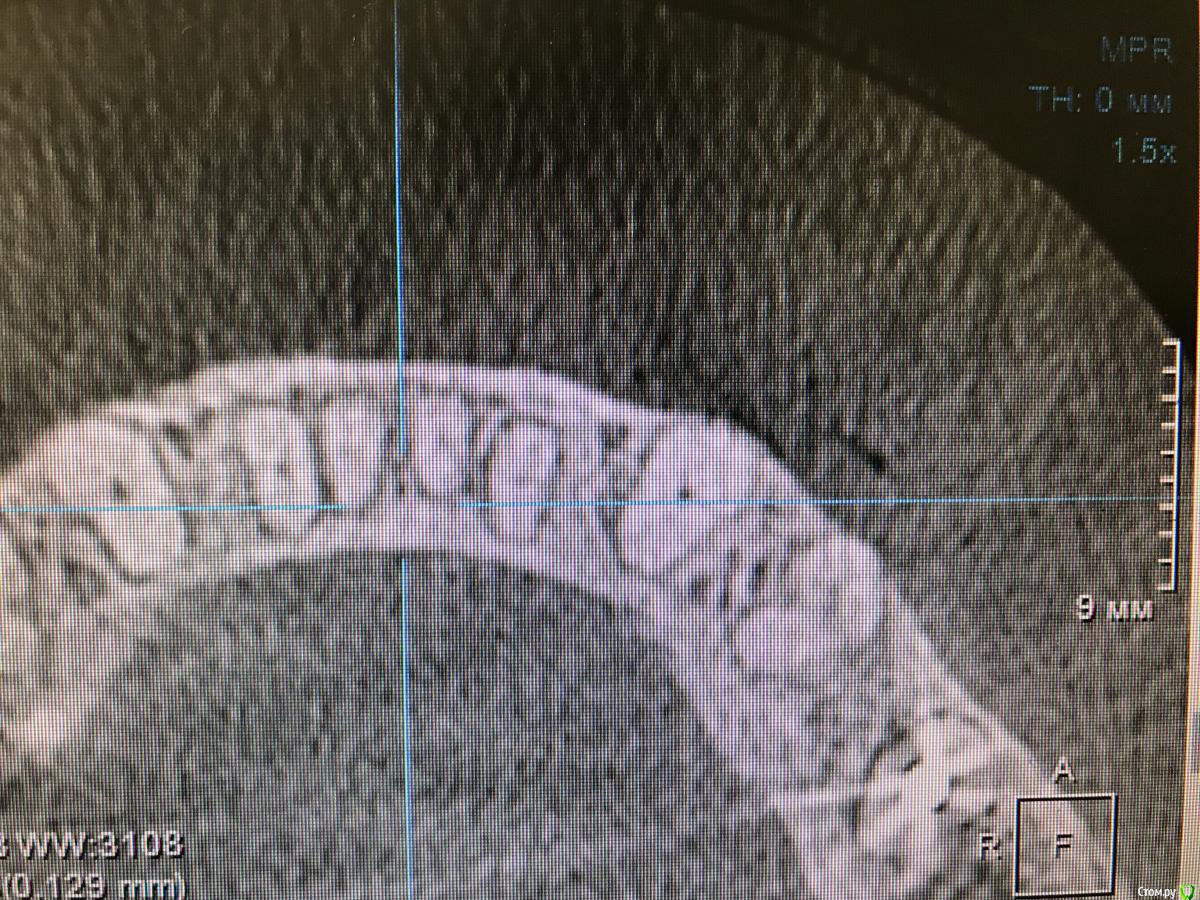

колесников Опубликовано 15 марта, 2019 Автор Поделиться Опубликовано 15 марта, 2019 Вот так выглядит интегрированый графт и соответственно не созревший. Время ожидания примерно равнозначное Ссылка на комментарий

колесников Опубликовано 16 марта, 2019 Автор Поделиться Опубликовано 16 марта, 2019 (изменено) Ну как бы тут все очевидно. Слева стала костью,справа нет. Но должен вам отметить,что даже в случае неудачи (как кажется)потери нет. Задача стояла не увеличить объём для имплантации или укрыть Имплант,а снять напряжение с вершины гребня и дать созреть десне. Имплант в нативной кости,он интегрирован,десна успела созреть за это время,возможно будет не так объёмно как хотелось бы,но у меня в запасе этап раскрытия ,фдм зарос ,есть с чем поработать. Все что не интегрировалось ,лизируется самостоятельно,выскребать ничего не нужно,ещё подождать. Изменено 16 марта, 2019 пользователем колесников Ссылка на комментарий